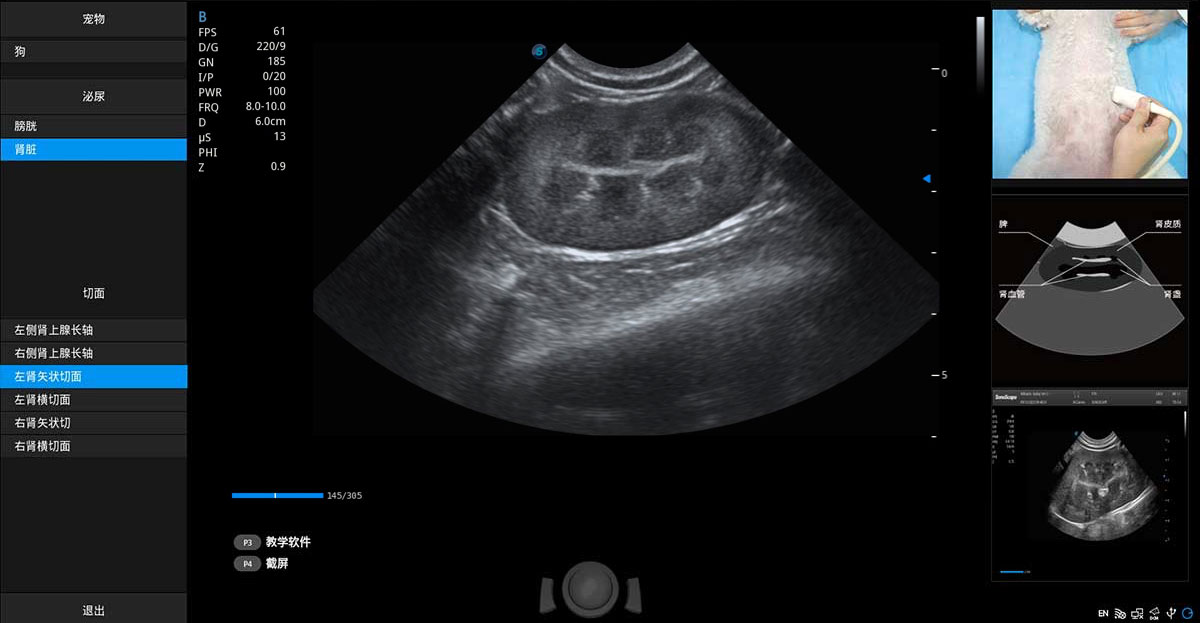

提供解剖示意圖、標準超聲圖像、掃查手法涂和操作者實時檢查圖像,指導操作者進行標準切面的正確掃查。